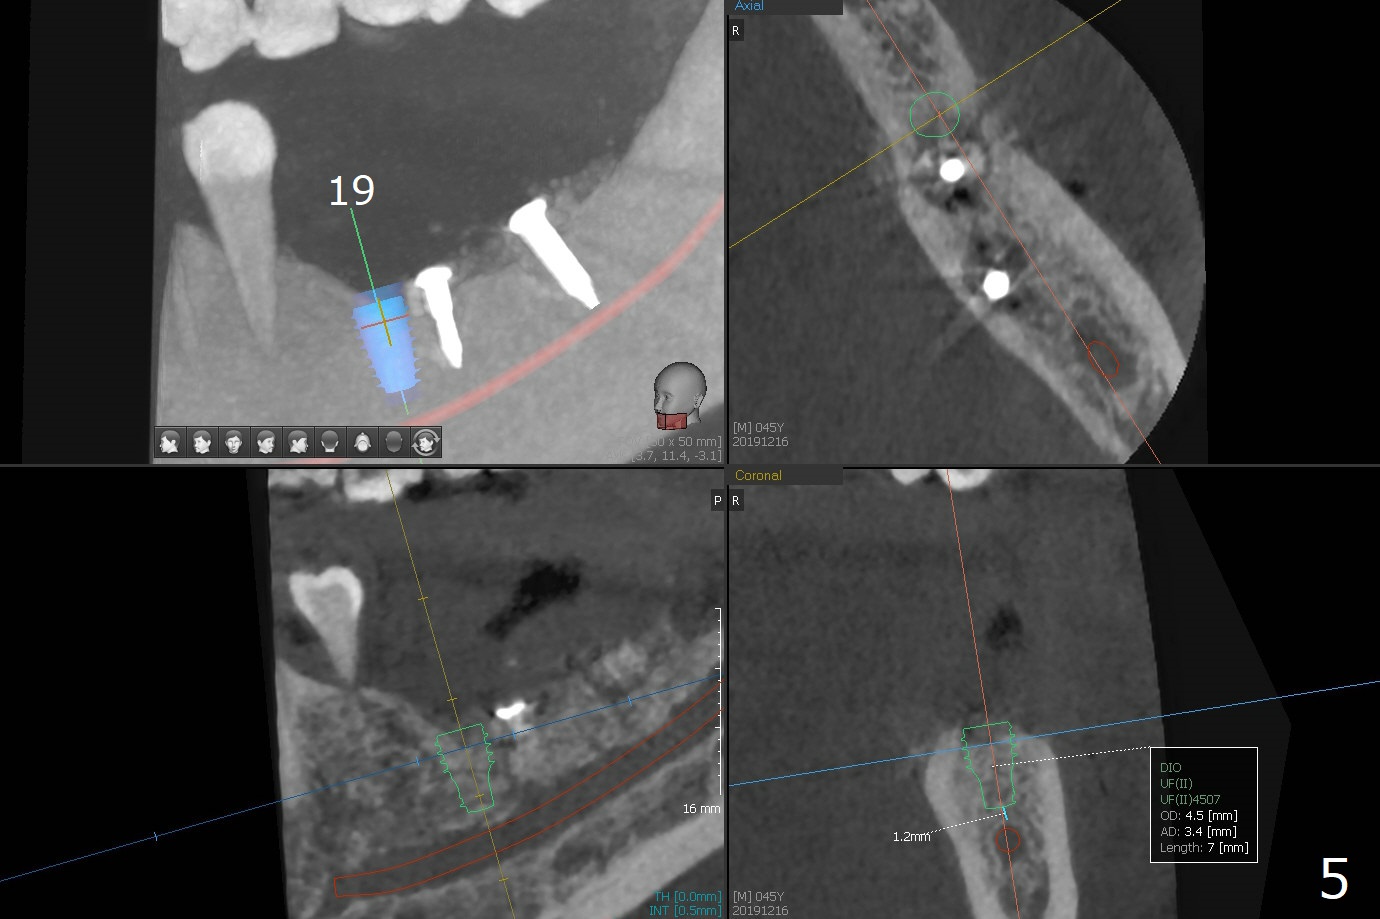

While the implant at #18 is easily removed, the one at #19 is superficial with buccal nonkeratinized gingiva (Fig.1). The latter is removed. Two small pieces of onlay graft is harvested from the left ramus and fixed in the defects with pins (Fig.2), surrounded by allograft with PRF. Since the pin at #18 looks violating the Inferior Alveolar Canal (Fig.2 C), CT is taken. In fact the pin perforates the lingual plate at #18 (Fig.4, as compared to Fig.3 (#19)). It leaves in place. Postop the wound dehisces with loss of allograft and exposure of the screws. The wound heals gradually mesiodistal with exposure of #18 screw 2.5 months postop. Follow up is disrupted by coronavirus pandemic.

It appears that short implants could be placed mesial to the original sites (Fig.5,6), 5x6 and 5x5 mm at #19 and 18, respectively, with guide as lingual as possible. The exposed buccal threads will be covered by 3-D Bond (Fig.9 white line, post decortication (red)), collagen plug and PGA suture. Healing screws are most likely used, although healing abutments should be prepared if they help wound closure.